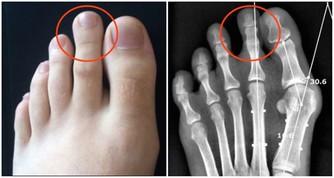

調查發現,在各類排毒產品和相關文章中,出現頻次最高的“毒”分別是:宿便、自由基、尿酸、乳酸、肌酐、膽固醇、脂肪等。這些物質有一個共同點——都是人體的代謝產物。但代謝產物並不等於毒。